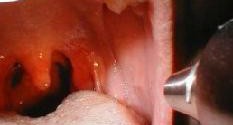

Читать »Герпесная ангина, что делать и как лечить в домашних условиях?

Герпесная ангина возникает в результате действия энтеровирусной инфекции. Ангина, вирусного генеза — тонзиллит, будет называться герпетическим, хотя никакого отношения к вирусу герпеса он не имеет.